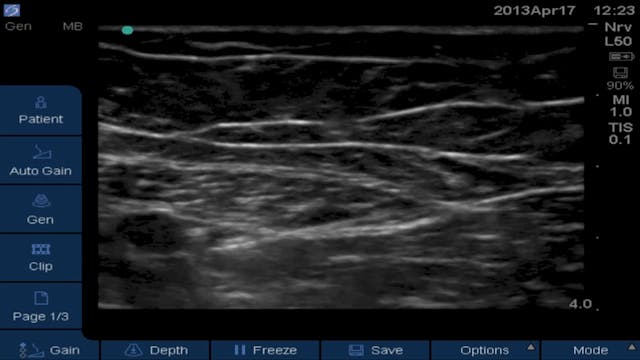

Part 2 of 3: Can a Saphenous/Adductor Canal Block Replace a Femoral for ACL? Saphenous/Adductor Canal Block

Saphenous/Adductor Canal • 5m 40s

In this video Brandon Winchester unsuccessfully attempts to block the posterior division of the obturator nerve by way of a mid-thigh adductor canal infiltration.